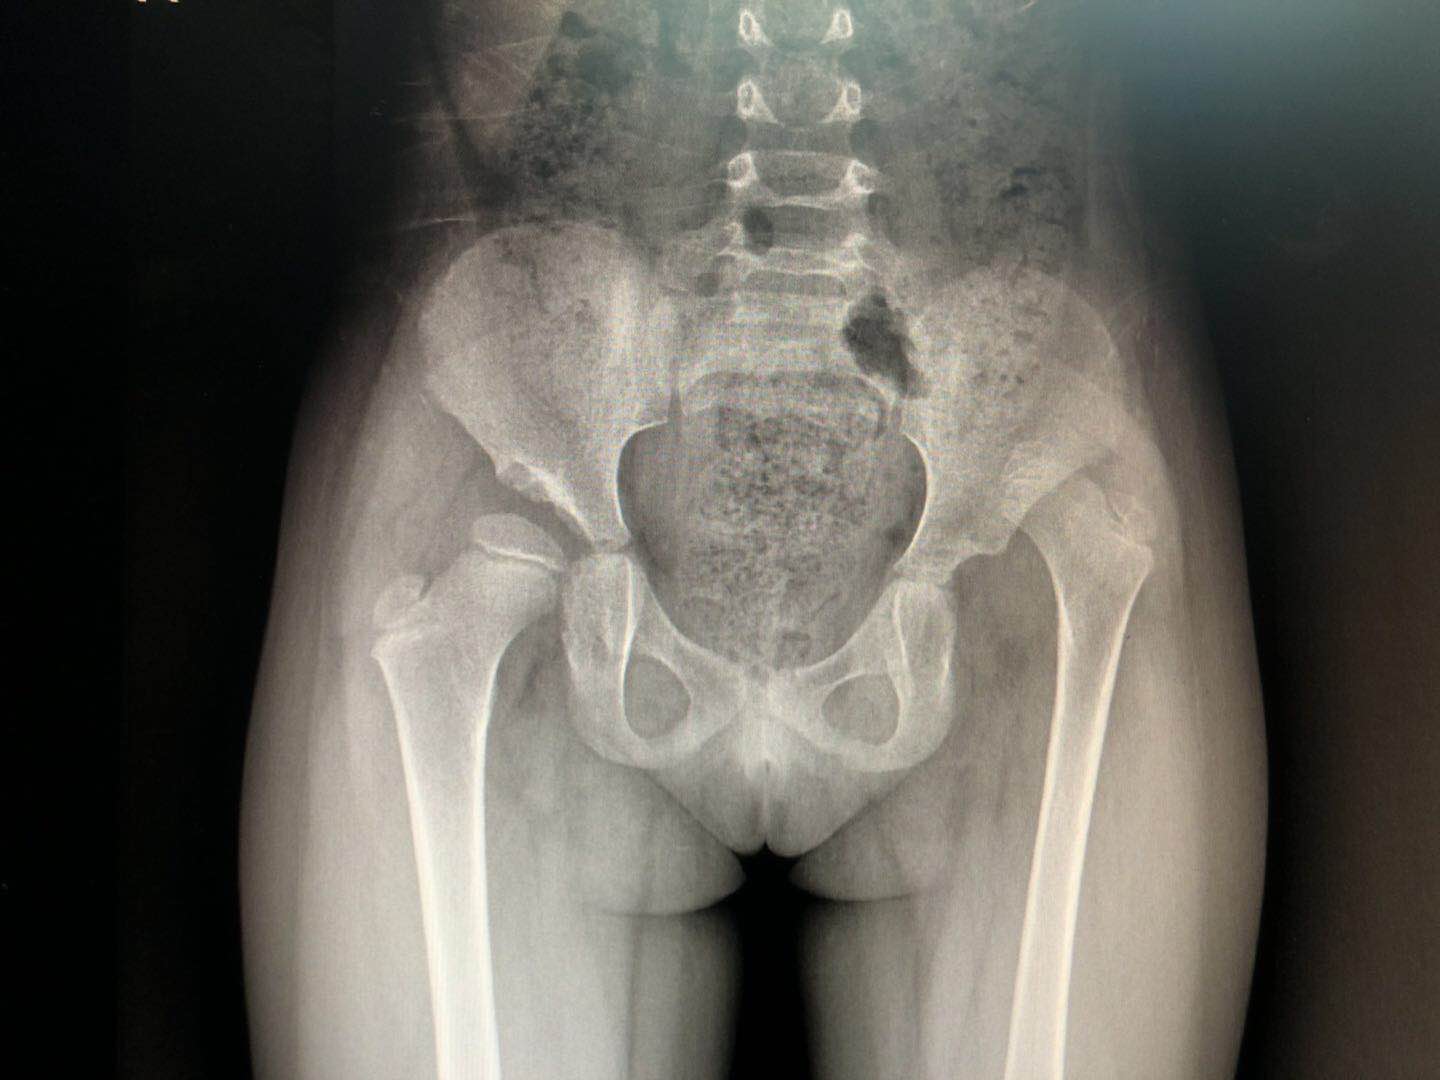

入院后医院给小李拍了个骨盆正位片结果如下:

入院的骨盆正位片

人体基本上是一个大致对称的解剖结构,但小李的这个照片,明眼人都看得出来,左边的脚“往上走”了,也就是说左边的脚短了许多,这个在临床上叫做髋关节脱位,看不懂的朋友们可以跟文章的第一个正常人体的骨盆正位片做对比。